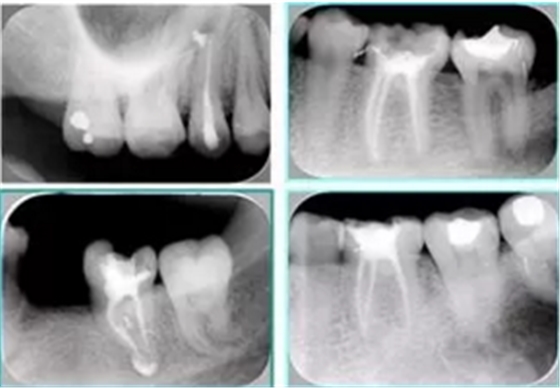

2. X 線片

共有 4 張 X 線片,分別是術(shù)前、診斷絲 、主牙膠尖確認(rèn)、術(shù)后。

( 1 )術(shù)前:術(shù)前 X 線片用來了解牙齒的大概情況。術(shù)前預(yù)期為多根牙時 X 線片應(yīng)偏頭拍攝。

( 2 )診斷絲:根據(jù)術(shù)前 X 線片進(jìn)行開髓、根管的初步預(yù)備后,需要插入診斷絲,用來指示工作器械位置。常用 10 號或 15 號擴(kuò)大器作為診斷絲插入牙髓腔。

( 3 )主牙膠尖確認(rèn):通過術(shù)前預(yù)期和診斷絲診斷,明確工作長度、牙根走向,進(jìn)行根管預(yù)備。之后應(yīng)進(jìn)行主牙膠尖(中銼)確認(rèn),已明確根管是否適合充填。

( 4 )術(shù)后:觀察治療效果。